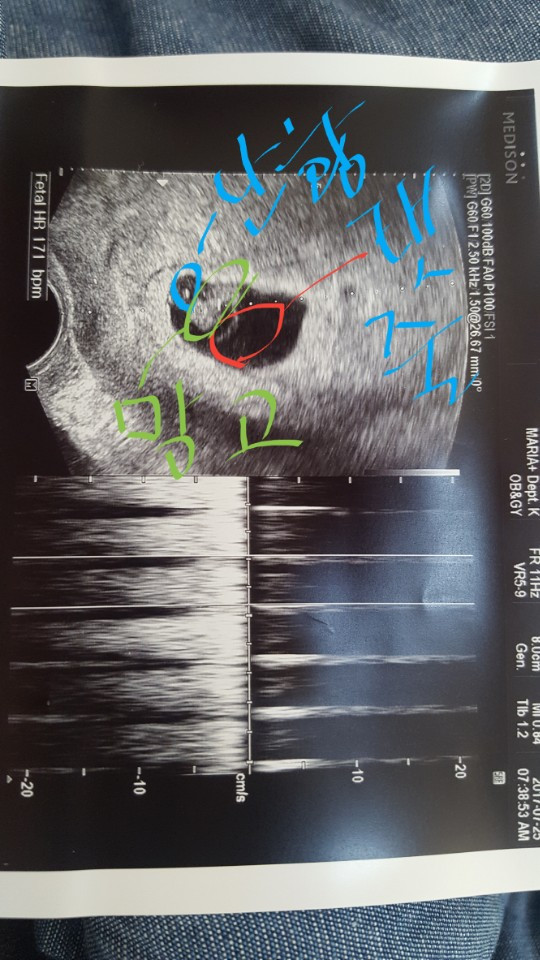

아내 몸속에 우리가 빚은 생명체를 확인한 2017년 6월 16일 금요일.

임신 소식을 듣고 아내와 기쁨을 나눈 후 서재에 꽂혀 있는 대학교 2학년 수업교재 발달심리학 책을 들춰봤다. 그리고 10년 전쯤 일이 떠올랐다. 알고 지내던 임상심리전문가분과 이런저런 이야기를 하는 도중 빛바랜 다이어리 몇 권을 보여주면서 글로 배운 발달과 실제 경험하는 것의 차이를 알고 싶어서 아이를 임심 한 후부터 매일 일기를 쓰셨다고 말하면서 학문과 실제 경험은 다르다고 알려주셨던 기억이다. 위대하고 존경스러운 실천이라 감탄하면서 나도 언젠가 내 아이가 생기면 일기를 써봐야지 라고 다짐했었다. 그래서 망고(태명) 일기를 끄적였지만 중간에 포기하고 말았다. 그리고 망고가 태어나기 전에 책 한 권을 출판해보자는 목표도 세우고 글쓰기 모임을 참가하며 노력했지만 다온이가 태어났을 때 책은 없었다.

성별을 알기 전에는 조인성과 김태희 성별을 알고는 김태희를 상상했던 망고(태명), 태어난 다온이를 보고 알게 된 '유전의 힘은 강하다'